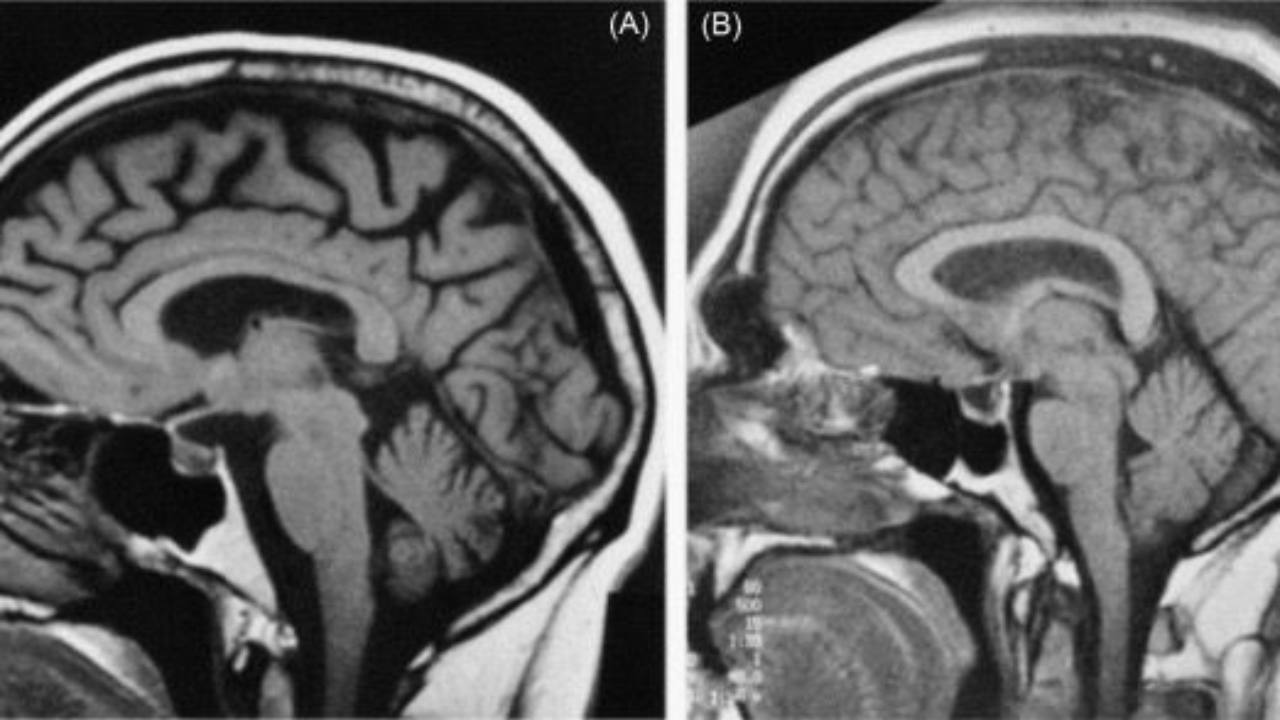

Brain Atrophy & AMD

Could this be a new biomarker?...

An article published in the American Journal of Ophthalmology last week reveals a significant association between outer retinal thinning and brain atrophy in early age-related macular degeneration (AMD). This correlation, particularly strong in vision-related b...